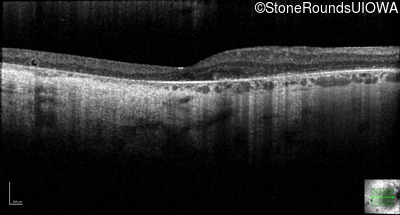

Optical Coherence Tomography - Left - 20/32 -2

Exemplar / OCT Stack

OCT Stack